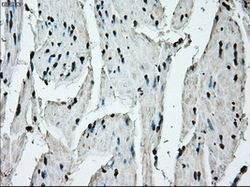

- Immunohistochemical staining of paraffin-embedded lung tissue using anti-ERCC1 mouse monoclonal antibody. (Dilution 1:50).